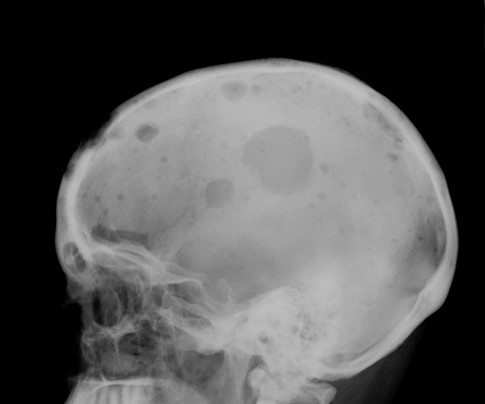

A Isabel, recientemente, le encontraron una lesión en el cráneo de tipo lítico, como un hueco, en sacabocados, típica del Mieloma Múltiple. Posteriormente, el diagnóstico se ha completado con un estudio analítico, especialmente de las proteínas, para valorar esa alteración en la fracción de las inmunoglobulinas del proteinograma, seguido de aspirado de médula ósea y radiológico completo.

El caso del Mieloma no es distinto, ya que el apellido múltiple matiza, pero no cambia el diagnóstico, que se caracteriza por una aparición multicéntrica de lesiones, los plasmocitomas.

Estos plasmocitomas son producidos por células plasmáticas (derivadas de los linfocitos B), que producen inmunoglobulinas, las proteínas que normalmente nos protegen de las infecciones.